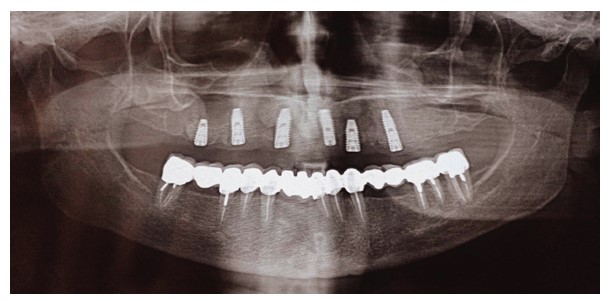

A 62-year-old female patient presented for maxillary rehabilitation with an implant-supported fixed prosthesis. Clinical examination revealed a failing conventional fixed partial denture extending from tooth #14 to #21, exhibiting significant gingival recession and radiographic evidence of periapical pathology. Preoperative cone-beam computed tomography (CBCT) using a Planmeca ProMax 3D unit demonstrated a well-defined radiopaque lesion measuring 1.5 × 1.3 cm adjacent to tooth #16, with a buccal-palatal width of 8.2 mm and bone density measuring 1250 Hounsfield units (Fig. 1).

Preoperative OPG showing a radiopaque lesion on the right posterior maxilla.

OPG 6 months after surgery showing the success of the dental implant placed within the osteosclerotic area.